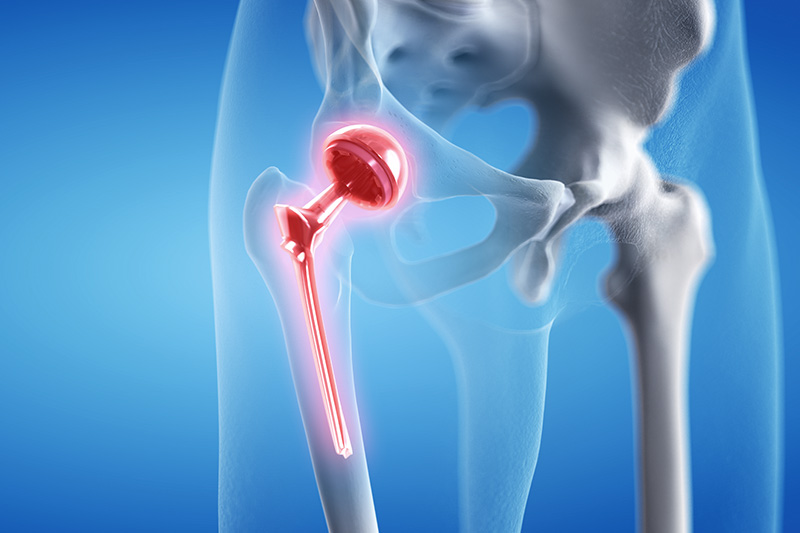

Revision hip replacement involves removing the old or damaged implant and replacing it with a new, advanced prosthesis to restore stability and comfortable movement. This surgery is more complex than primary hip replacement and requires specialized skills, precision, and careful planning.

Common reasons for revision surgery include implant wear, infection, dislocation, bone loss, fracture, or persistent pain. With expert evaluation and the latest surgical tools, HappyKnees ensures accurate diagnosis and effective long-term solutions.

Revision hip replacement requires a high level of expertise, and Dr. Akash Saraogi is known for successfully treating complex hip cases with advanced surgical techniques. At HappyKnees, we use specialized revision implants, bone reconstruction techniques, 3D imaging, and minimally invasive approaches wherever possible to ensure optimal patient outcomes.